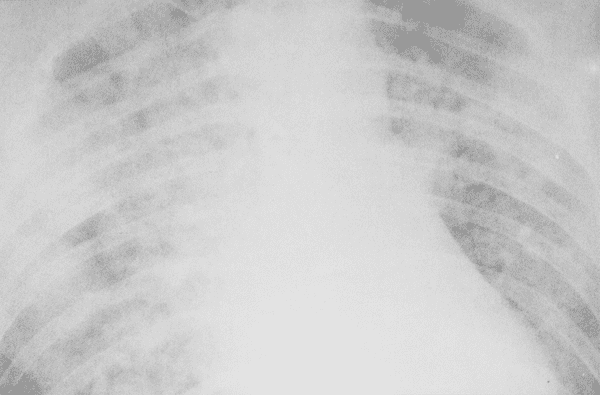

При проведении рентгенографии грудной клетки уже в начале болезни обнаруживают множественные, порой обширные воспалительные инфильтраты, особенность которых в быстром слиянии и распространении за пределы первичного очага воспаления; иногда долевые уплотнения.

Дальнейшее развитие болезни приводит к развитию осложнений: дыхательной недостаточности и острого респираторного дистресс-синдрома (ОРДС). ОРДС сопровождается выраженным тотальным воспалением легочной ткани, грубыми нарушениями дыхания, кислородной недостаточностью и развитием отека легких. Нередко развитие такого осложнения является смертельным для пациента.

Респираторный дистресс-синдром